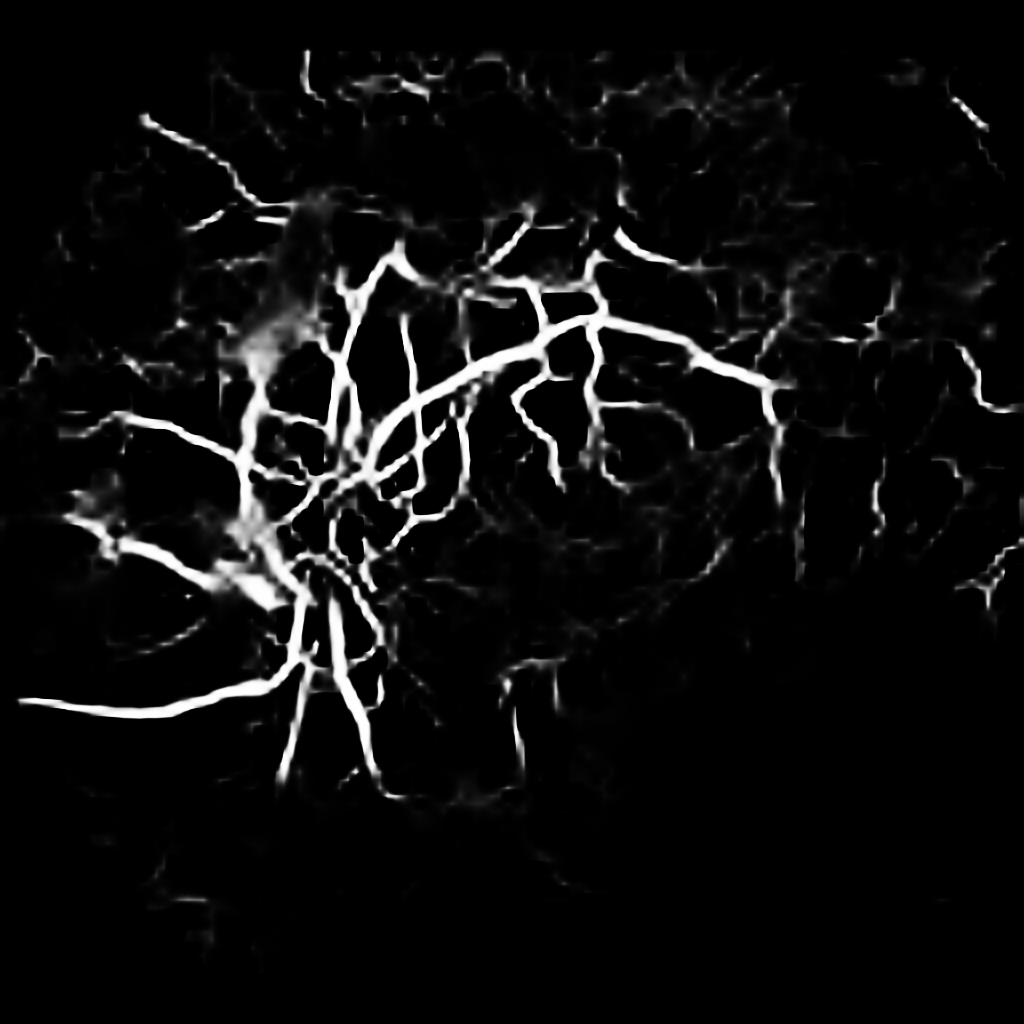

For completeness, and to test the robustness of our method, the models were also tested with several images sourced from Google™. We purposefully sourced extremely poor quality images (i.e. images with low contrast, speckle artefacts, etc), as well as images of pathological cases (i.e. Exdudates, Hemorrhages, etc). As there are no ground truth labels, only a qualitative assessment can be made of the results shown in Figure 2. In all cases, the models have accurately segmented the vessel structure whilst ignoring imaging artifacts and pathological lesions. This is very evident in the case of (5) and (6) where no vessels were segmented in areas of severe hemorrhaging.

{L to R: (1) Healthy, (2) Unhealthy, (3) Speckle Artefacts, (4) NPDR, (5) PDR, (6) Hemorrhages}